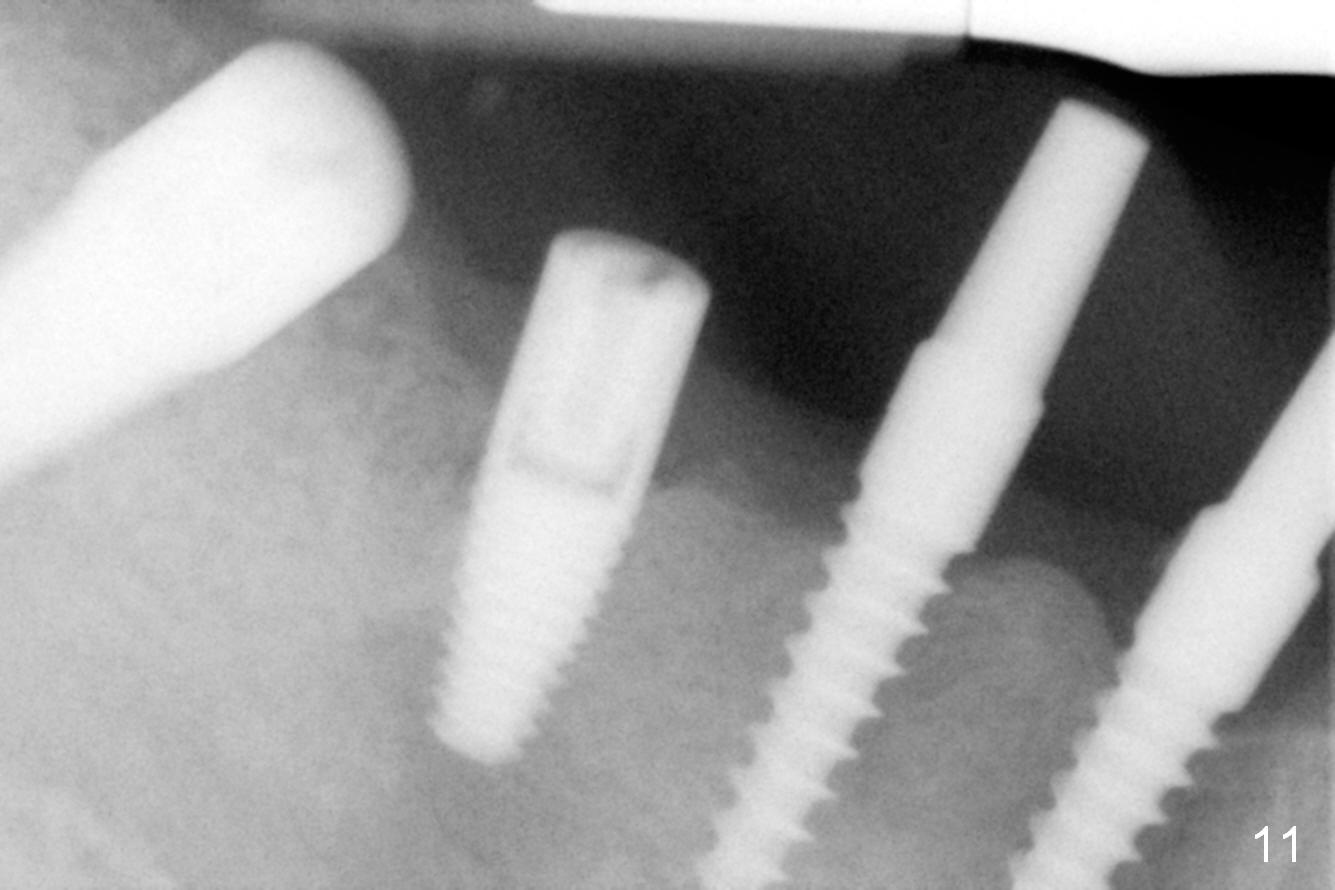

The lower right bridge (from canine (Fig.2: 3) to 1st molar (Fig.1: 6)) fails while a 77-year-old man is undergoing chemotherapy for urinary bladder cancer.  The abutments of the bridge are extracted without plan for implants (Fig.4).   Four months later, the patient returns for implants (Fig.3), but the ridge is narrow (Fig.5).  While 2 of 3x14 mm 1-piece implant are placed at the canine and 1st bicuspid sites, 2 piece ones at the 2nd bicuspid and 1st molar sites (Fig.6: 3.5x11 mm, 5x14 mm).  Soft (Fig.7-10) and hard (Fig.11) tissues heal 1 week (Fig.7) and 4 months (Fig.8-11).  There is minimal bone resorption 1 year 7 months post cementation (Fig.12,13, non-splinting).  It appears that narrow diameter implants are a valid solution to narrow ridge at the sites of the lower canine and premolar.  As long as there are enough implants for function, the crowns are not necessary to be splinted.  Surprisingly, the patient starts flossing after implant restoration.  Retrospectively an immediate provisional bridge should have been fabricated.